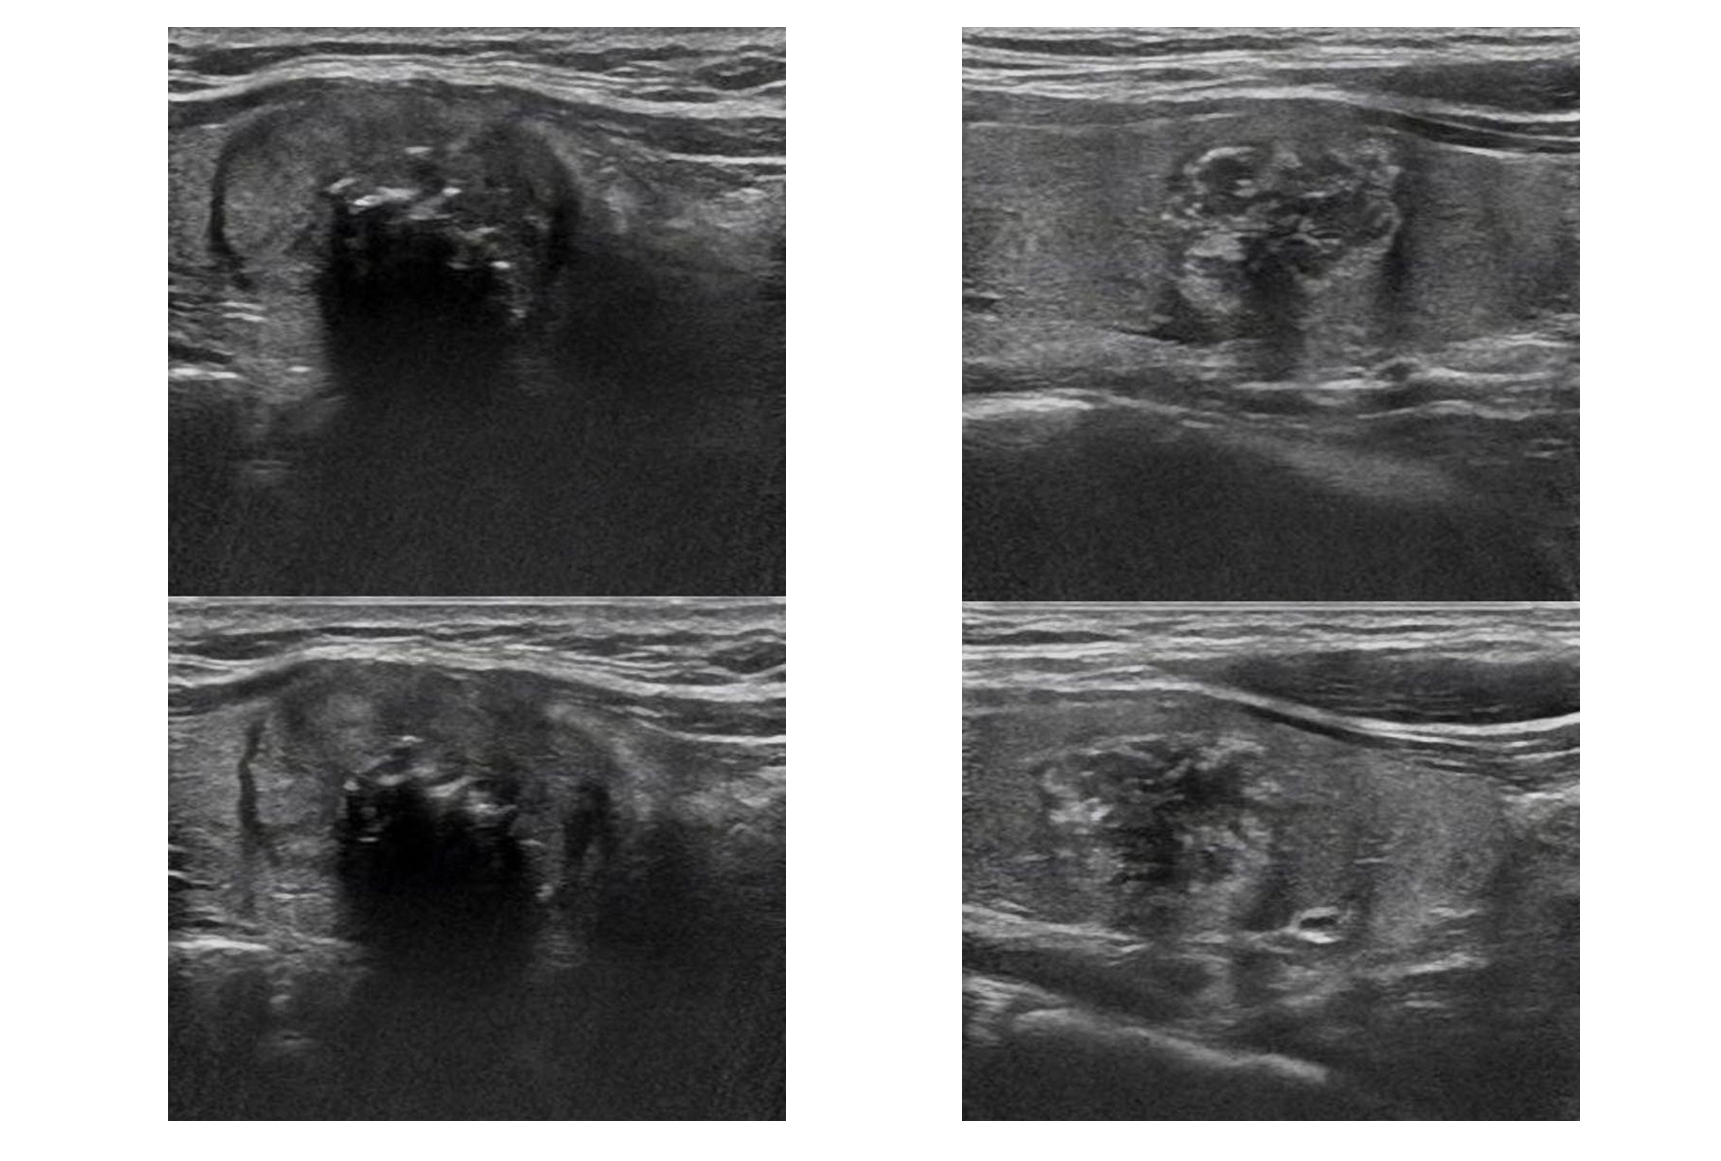

此次比赛选用的超声片均来自于北京友谊医院真实的病例,每张片子都是经过“金标准”检验的,其中良性患者需要同时满足穿刺结果为良、基因检测为阴性、随访时间超过半年三个条件。恶性肿瘤患者则是术后的病理检测确诊为恶性。医生们通过手机回答问卷的形式,依据结节超声图像特点对100套超声图像做出良恶性判定,每答对一次得1分,全部答对得100分。“视诊通”和医生同台竞技,会务组按照同样的评分标准为“视诊通”打分。最后,按照正确率进行竞技排名。